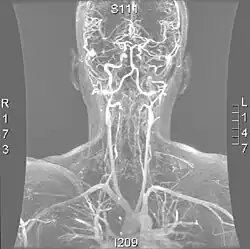

Uma reconstrução das artérias vertebrais a partir de uma tomografia computadorizada, vista de frente. Do fundo, V1 é da artéria subclávia para o forame, V2 é do forame para a segunda vértebra, V3 está entre os forames até à entrada no crânio e V4 está dentro do crânio embutido na dura-máter . Eles fundem-se na artéria basilar, que então se divide na artéria cerebral posterior.

As artérias vertebrais surgem da artéria subclávia e passam pelo forame transverso das seis vértebras superiores do pescoço. Depois de sair no nível da primeira vértebra cervical, o seu curso muda de vertical para horizontal, e então entra no crânio pelo forame magno. Dentro do crânio, as artérias fundem-se para formar a artéria basilar, que se junta ao círculo de Willis. No total, três quartos da artéria estão fora do crânio, área em que tem uma elevada mobilidade devido ao movimento rotativo do pescoço sendo, portanto, vulnerável a traumas. A maioria das dissecções ocorre no nível das primeira e segunda vértebras. A artéria vertebral supre uma série de estruturas vitais na fossa craniana posterior, como o tronco cerebral, o cerebelo e os lobos occipitais. O tronco cerebral abriga várias funções vitais (como a respiração) e controla os nervos do rosto e do pescoço. Já o cerebelo, este faz parte do sistema difuso que coordena o movimento. Finalmente, os lobos occipitais participam do sentido da visão.[1]

Angiografia por ressonância magnética dos vasos do pescoço numa pessoa com síndrome de Ehlers-Danlos tipo IV; A ressonância mostra uma dissecção da artéria carótida interna esquerda, dissecção de ambas as artérias vertebrais nos seus segmentos V1 e V2 e uma dissecção do terço médio e distal da artéria subclávia direita. Esses episódios marcantes de dissecção são típicos desse subtipo "vascular" da síndrome de Ehlers-Danlos.

Existem várias modalidades de diagnóstico para demonstrar o fluxo sanguíneo ou a ausência dele nas artérias vertebrais. A principal é a angiografia cerebral (com ou sem angiografia de subtracção digital).[3][13][14] Isto envolve a punção de uma grande artéria (geralmente a artéria femoral) e o avanço de um cateter intravascular através da aorta em direcção às artérias vertebrais. Nesse ponto, é injectado radiocontraste e o seu fluxo a jusante é capturado na fluoroscopia (imagem contínua de raios-X). O vaso pode parecer estenótico (estreito, 41–75%), ocluído (bloqueado, 18–49%) ou como um aneurisma (área de dilatação, 5–13%).[1] A angiografia cerebral é um procedimento invasivo e requer grandes volumes de radiocontraste, o que pode causar complicações como nefropatia induzida por contraste.[15] A angiografia também não demonstra directamente o sangue na parede do vaso, ao contrário das modalidades mais modernas.[2] O único uso restante da angiografia é quando o tratamento endovascular é contemplado.[1]

Os métodos mais modernos envolvem angiografia por tomografia computorizada, denominada angiotomografia (ATC ou angio-TC) — e ressonância magnética (RM). Estes métodos requerem uma menor quantidade de contraste e não são invasivos. A angiografia por TAC e a angiografia por RM são mais ou menos equivalentes quando usadas para diagnosticar ou excluir uma dissecção da artéria vertebral.[13] A ATC tem a vantagem de mostrar certas anormalidades mais cedo, tende a estar disponível fora do horário de expediente e pode ser realizada rapidamente.[1] Quando a angiografia por RM é usada, os melhores resultados são obtidos no cenário T1[2] usando um protocolo conhecido como "supressão de gordura".[3] A ecografia Doppler é menos útil, pois fornece poucas informações sobre a parte da artéria próxima à base do crânio e no forame vertebral, e qualquer anormalidade detectada na ecografia ainda exigiria confirmação através de um TC ou RM.[1][2][3]